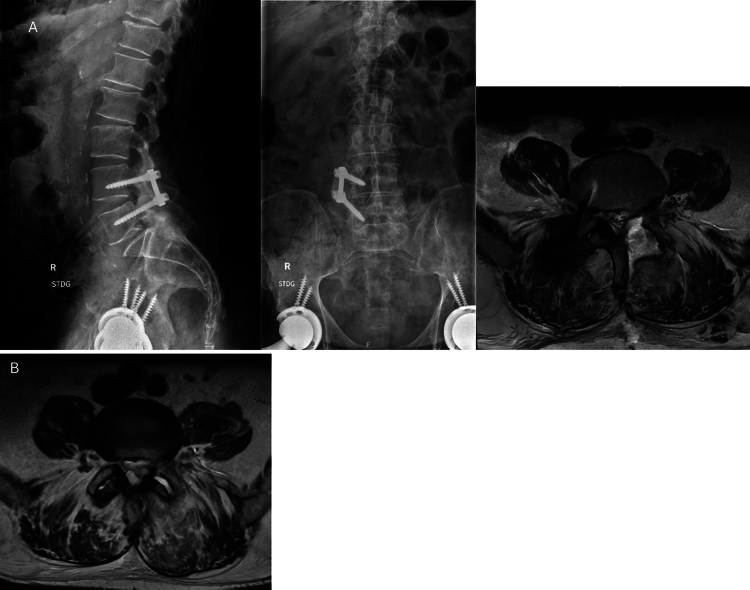

Observations: A 70-year-old male with a past medical history of immunoglobulin A lambda smoldering myeloma degenerative lumbar disease who presented with low back and radicular lower extremity pain was found to have a left L4-5 septic facet cyst with extension to the epidural space. Intraoperative cultures were positive for Nocardia species. Staging workup revealed progression to high-risk-profile multiple myeloma.